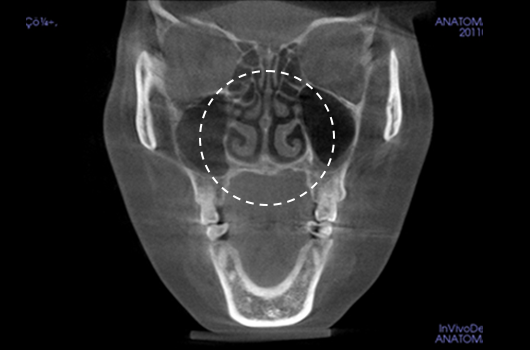

Operasi hidung CT 3D membantu pelaksanaan operasi hidung yang lebih canggih setelah menganalisis wajah secara cermat untuk menentukan mana yang terbaik.Analisis tiga dimensi digunakan untuk mengetahui keadaan secara umum, ukuran, bentuk, dan asimetri tulang hidung, tulang rawan septum hidung, dan jaringan kulit, yang tidak dapat ditentukan melalui konsultasi pada umumnya. Saat merencanakan revisi operasi hidung, kami dapat memeriksa elemen fungsional seperti deviasi septum hidung, bentuk implan yang ada, termasuk implan silikon, atau komplikasi dari operasi sebelumnya.

Pentingnya 3D-CT Scan pada Operasi Hidung

Dalam setiap konsultasi operasi hidung, Klinik Operasi Plastik Braun menggunakan 3D-CT scan untuk menganalisis isu-isu berikut dalam tiga dimensi: Rancangan bedah dapat dibuat lebih tepat dan potensi efek samping dapat berkurang dengan memahami lebih lanjut ukuran, bentuk, dan asimetri bagian hidung yang tak kasat mata dan struktur anatomi disekitarnya sebelum operasi.

1. Analisis tulang rawan septum dalam berbagai ukuran dan bentuk

2. Diagnosis dan tindakan untuk deviasi hidung dan deviasi septal

3. Analisis untuk lebar dan asimetri tulang hidung

4. Diagnosis Inferior turbinate asymametry dan pembedahan hidung tersumbat